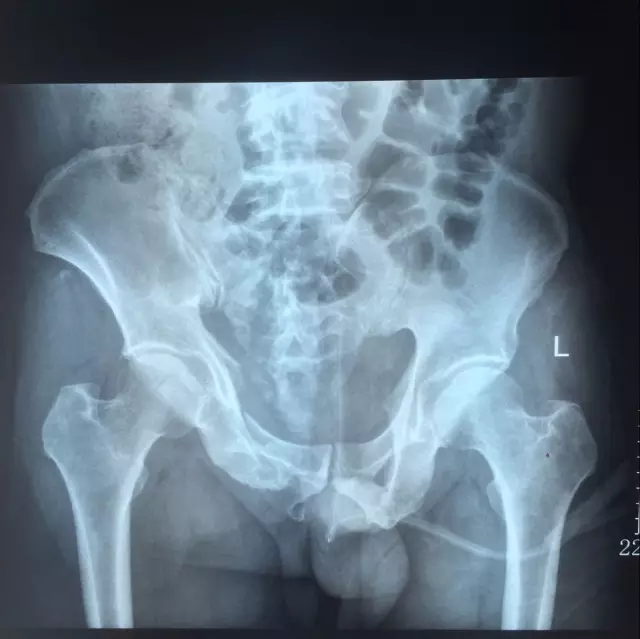

该患者为双前臂桡尺骨远端多发粉碎骨折,骨盆多发骨折(双侧耻骨上下支骨折、右髋臼骨折、右骶骨粉碎性骨折),腰椎多发骨折。骨盆骨折的手术治疗在创伤骨科而言,难度大、技术要求高,较容易出现相关并发症。

患者骨盆骨折术前X片及CT片情况